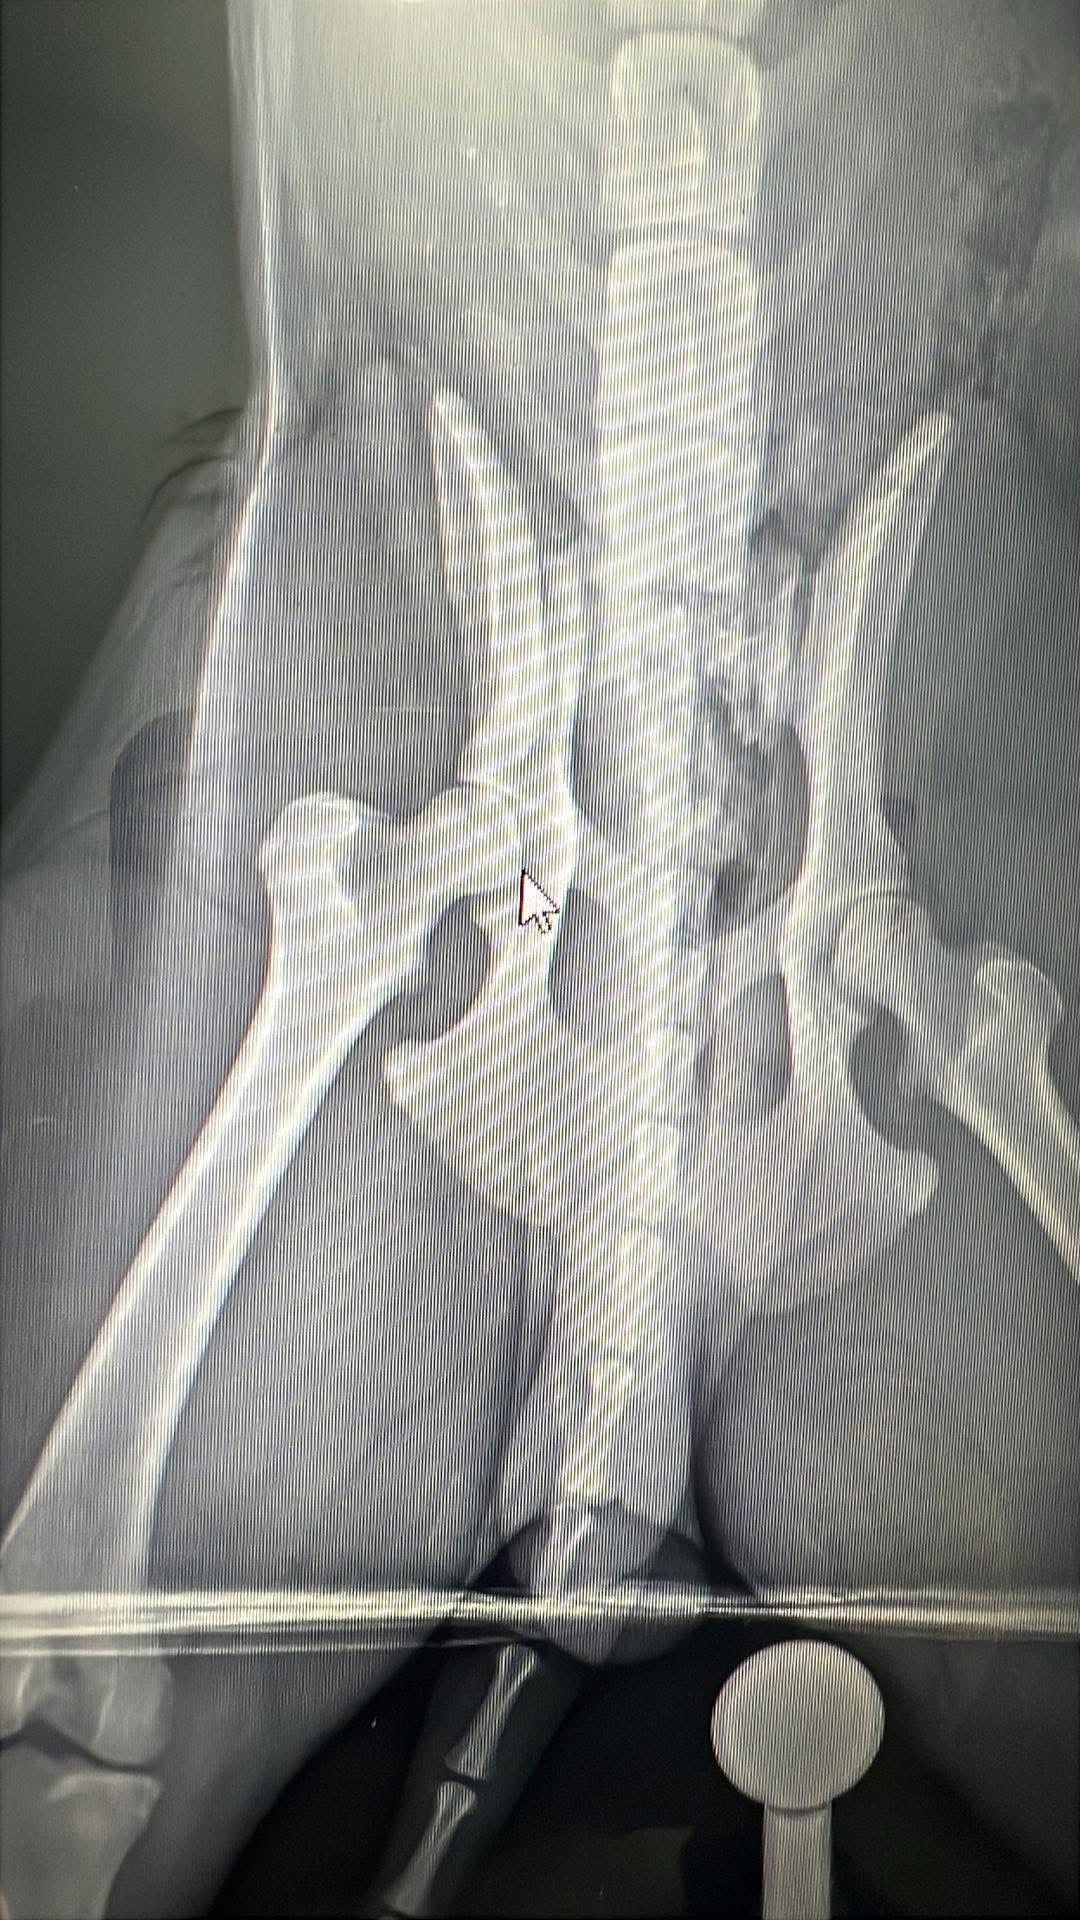

Toby has been with us since the day he was born, and he’s truly the sweetest, most gentle dog I’ve ever known. He’s a big part of our family, always bringing us joy and comfort. Recently, Toby managed to escape and was tragically hit by a car. The accident left him unable to walk, with a broken hip and two broken back legs. Watching him try his best to get up and move, despite the pain, is heartbreaking. He’s fighting so hard, and it’s clear he wants nothing more than to be back on his feet, playing and cuddling with us again.

Toby’s only chance at recovery is emergency surgery. Without it, he won’t be able to walk or enjoy the life he loves. The cost of the surgery is overwhelming for us, and we can’t imagine losing him when he’s trying so hard to stay strong. We’re reaching out to our community for help because we believe in the kindness of others and the power of coming together in tough times.

Toby’s only chance at recovery is emergency surgery. Without it, he won’t be able to walk or enjoy the life he loves. The cost of the surgery is overwhelming for us, and we can’t imagine losing him when he’s trying so hard to stay strong. We’re reaching out to our community for help because we believe in the kindness of others and the power of coming together in tough times.